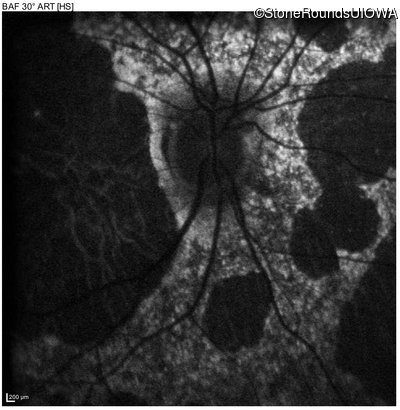

Blue Autofluorescence - Right - 10/200 sc

Exemplar

Blue Autofluorescence - Left - 10/125 sc